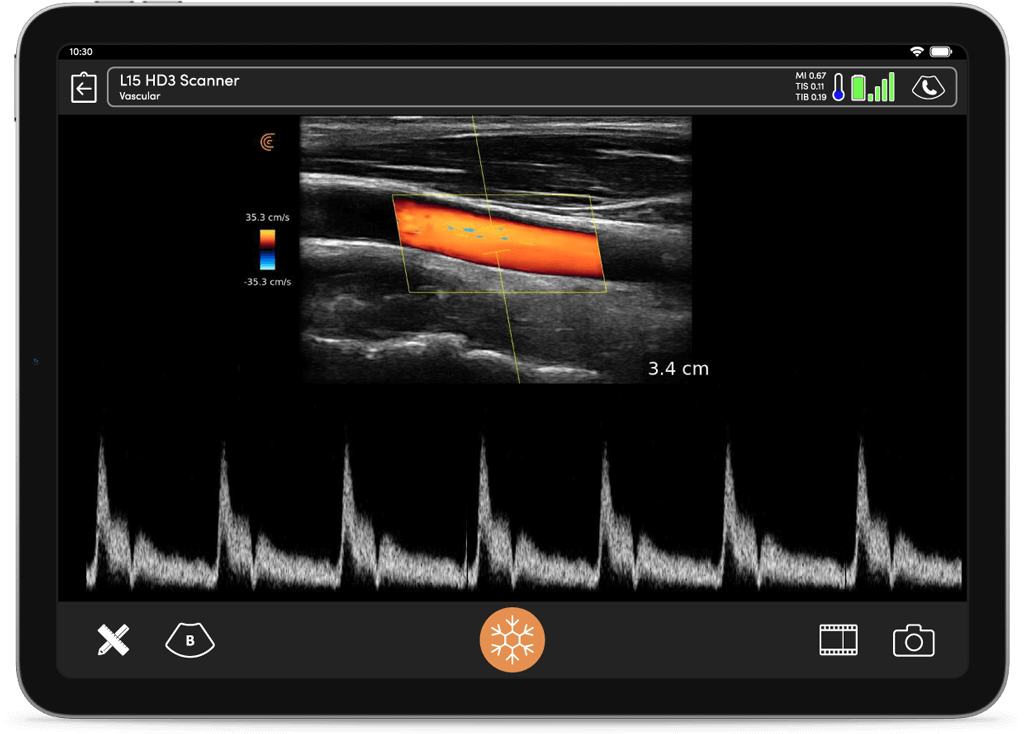

Mesurez et visualisez les informations clés du flux à travers une interface simple et intuitive.